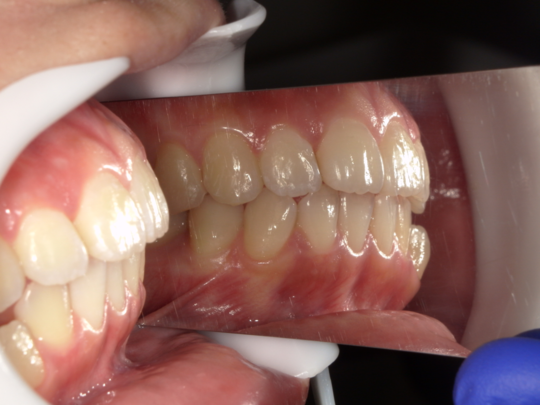

実例写真①

矯正前(横から見たところ)

矯正後(横から見たところ)